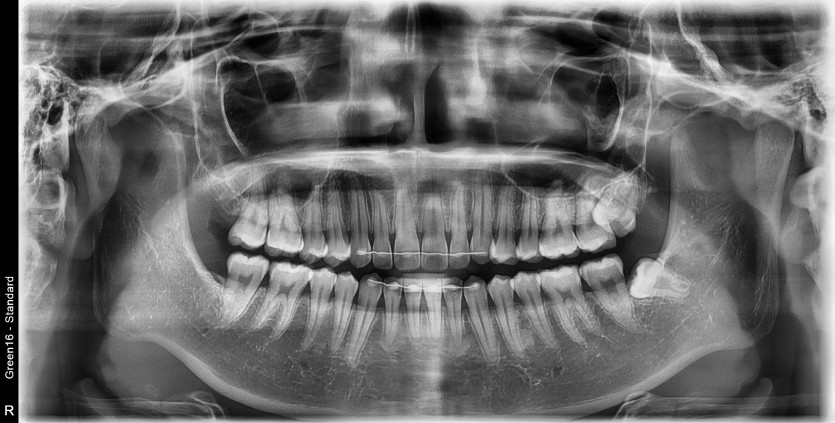

#28,38 사랑니 발치

구강 외과 전문의가 당일 발치했습니다.